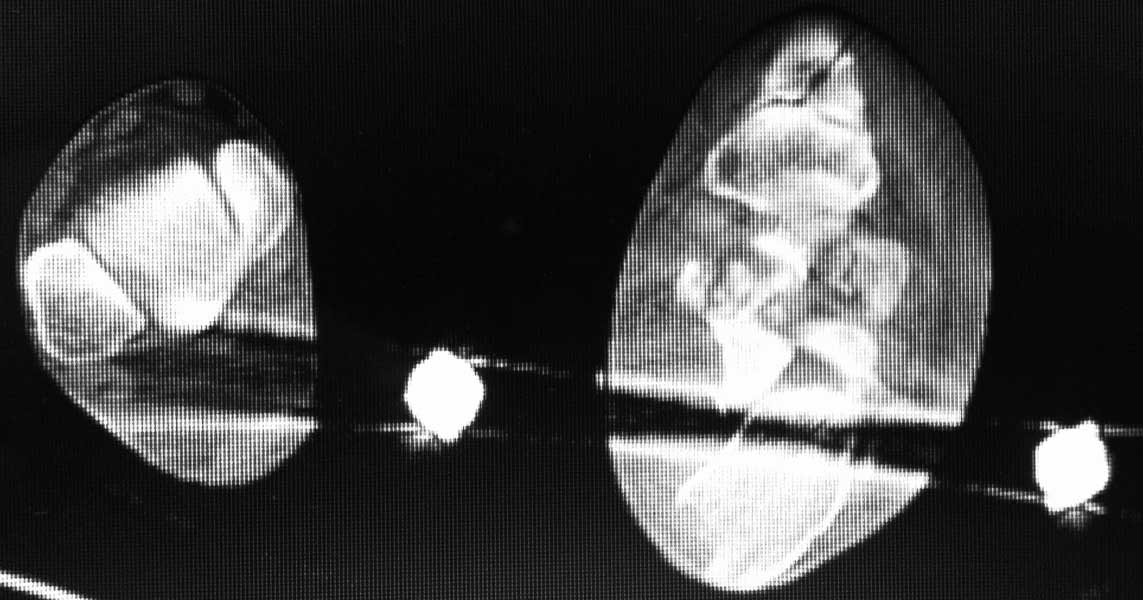

немного КТ

КТ